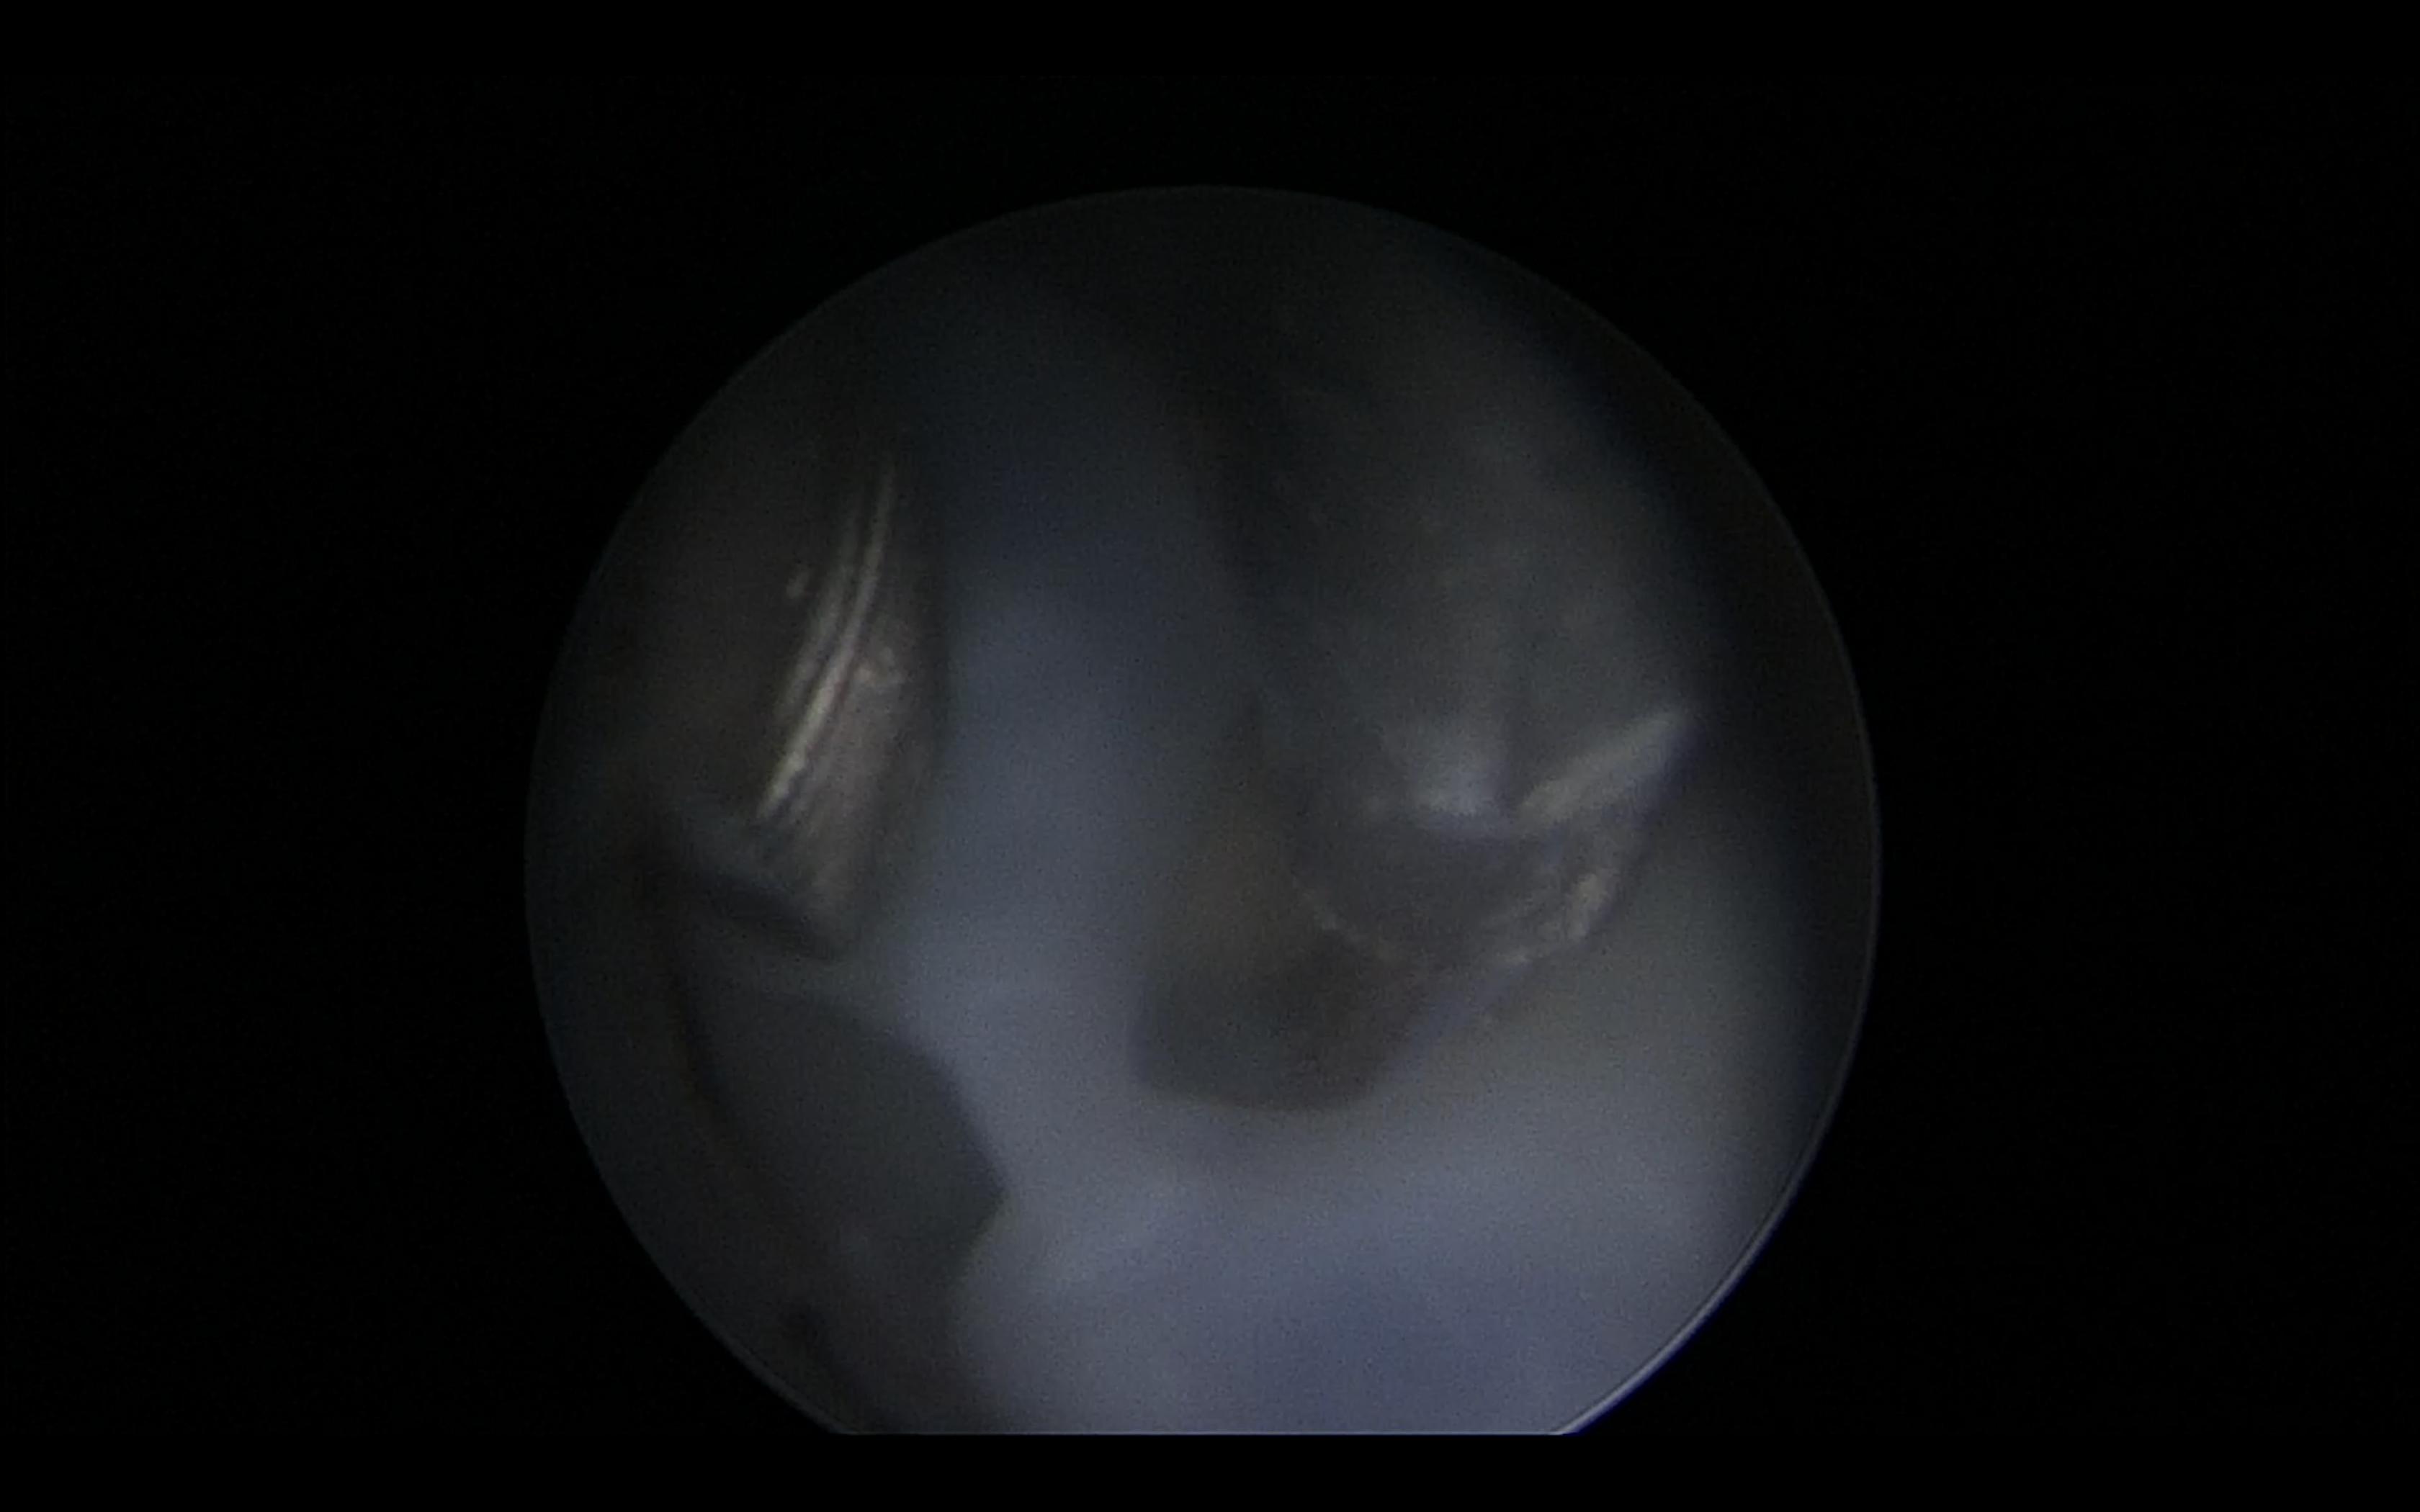

通过对病情进行详细分析,充分评估胎儿病情,孕妇及家属要求保留健康的大胎,姚若进教授决定为其实施胎儿镜下脐带电凝减胎术。据悉,胎儿镜是一种镜体内径只有1.7-2.2mm、套管直径3mm的光学纤维内窥镜,经腹壁、子宫壁进入羊膜腔,可以直接观察胎儿体表,并进行多种胎儿宫内治疗。胎儿镜手术是产科胎儿医学领域最高水平的技术操作之一,国外只有大型胎儿医学中心才有胎儿镜,国内近几年才有数家医院开展胎儿镜手术。

术前,湘雅医院胎儿医学团队进行多学科会诊,包括胎儿医学专科、新生儿科、麻醉科及手术室,针对胎儿的个体情况进行讨论并制定相应的处理策略。术中,专家们首先通过超声定位引导,将直径3mm Trocar经孕妇腹壁、子宫壁进入小胎儿羊膜腔内。在胎儿镜下,可以清晰地看到胎儿肢体、毛发,充分暴露胎儿脐带,然后置入脐带夹,钳夹脐带并电凝烧灼,阻断脐带血流。超声下见小胎胎心率减慢至5-10/min,大胎胎心率及彩色多普勒血流频谱正常,手术顺利完成。术后,小胎已无胎心,大胎在宫内状况良好,孕妇无胎盘早剥、胎膜早破等并发症。